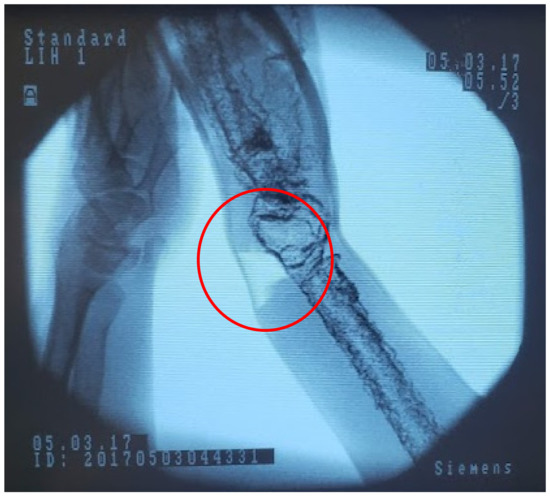

Figure 11.

Fluoroscope image of our phantom showing a tear in the ballistic gelatin (circled) after manipulation of the joint.

Overly aggressive manipulation of the wrist can result in degradation and tearing of the ballistic gelatin, seen in the lighter area circled in Figure 12. This can be seen as a feature, in that potential patient damage can result from using too much force to realign the fracture. Seeing this behavior in models can be used to further demonstrate to residents the potential difficulties of this commonplace procedure. To further the longevity of the phantom we would need to reinforce this area, which may impact the tactile feedback. We will continue weighing the advantages and disadvantages of this material behavior.